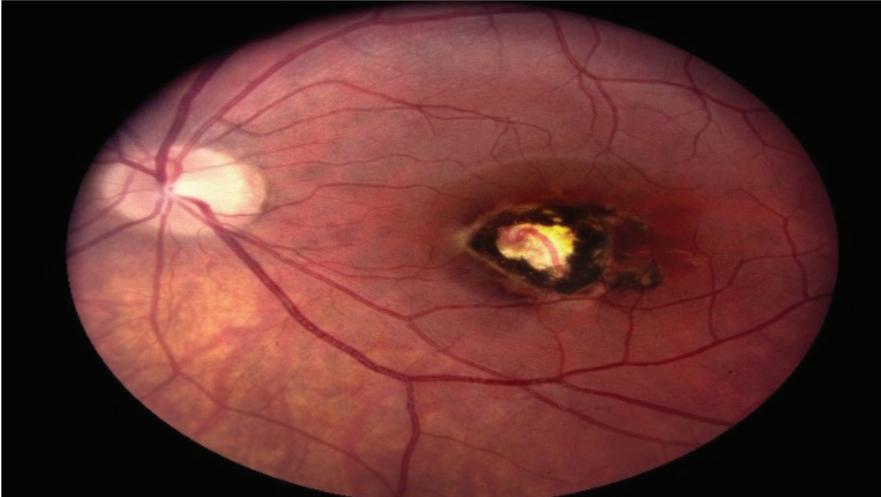

Many of us have heard the saying “your eyes are the window to your health”. This is true because many health conditions are first detected in the Retina (the retina captures the light that enters your eye and helps translate it into the images you see).

It is well known that diabetes and high blood pressure can damage blood vessels, which then causes damage to your retina. Inflammatory conditions can also cause damage. Eye injuries can damage your retina and the macula.

Signs of high blood pressure or hypertension, diabetes, brain tumors, and some forms of cancer are first evident in the retina. This is well before other signs appear throughout the body. Detecting such health issues early is vital in treating them. Finding retinal disorders as early as possible is critical to potentially preventing serious disease progression and even vision loss. In addition

to helping detect diseases early, retinal images provide a permanent and historical record of changes in your eye. With today’s electronic medical records applications, these images can be compared side-by-side, year after year, to discover even subtle changes and help monitor your health.

While dilation still constitutes a complete eye exam, retinal imaging for screening or to follow diseases, provides a complete picture of not only your eye health but also your health in general.

Retina exams are part of any comprehensive eye exam no matter what your age. But unless you need glasses or have other eye conditions, you may not be seeing an eye doctor regularly. If you don’t, you should start getting eye exams at least every 2-4 years. While screening retinal imaging is not covered by insurance, it will be covered if following a known retinal disease.

It’s the perfect retinal imaging system that provides TrueColor and widefield views in multiple imaging modalities. iCare EIDON provides unsurpassed image quality and a unique, live, confocal view of the retina in a dilation-free operation.

The iCare EIDON’s Ultra-widefield feature helps to preserve the sharpness and details even in the periphery, facilitating improved and early diagnosis.

• Widefield, ultra-high-resolution imaging • Capability to image through cataract and media opacities

A healthy retina is essential for maintaining clear vision and overall eye function. These photographs can be used to evaluate the health of the optic nerve, vitreous, macula, retina and surrounding blood vessels to diagnose conditions such as:

• Macular Degeneration

• Hypertensive Retinopathy

• Vitreous Detachments

• Diabetic Eye Disease

• Macular Holes

• Glaucoma